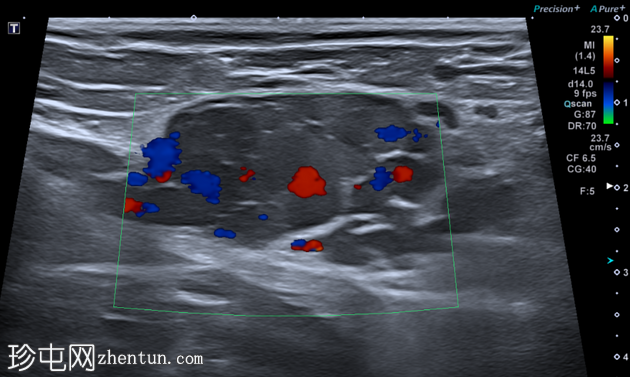

超声显示一个卵圆形低回声肿块,内部有多处分隔,与腹膜内脂肪不符,且未见蠕动(提示肠袢疝出)。

B超显示该结构内血流缓慢。

虽然本次图像未达到最佳效果,但彩色多普勒显示内部血流信号增强,Valsalva动作后血流信号增加,证实该结构为静脉性质。